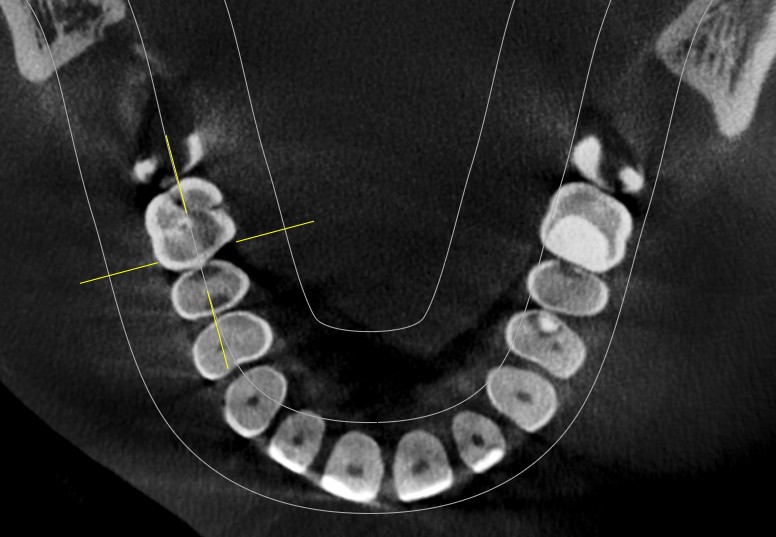

门诊经常遇到常年把碳酸饮料当水喝的患者,严重损伤了牙齿的健康,检查发现牙齿脱矿.龋坏特别严重,特别是邻面龋坏,治疗也非常麻烦,很多情况下,简单的补牙都解决不了长久性问题,想要经久耐用,可以选择嵌体,高嵌体,全瓷牙冠修复,更重要是杜绝不良嗜好;有图有真相!我们采用德国西诺德瓷睿刻即刻修复系统,等待1小时,完成当日修复。